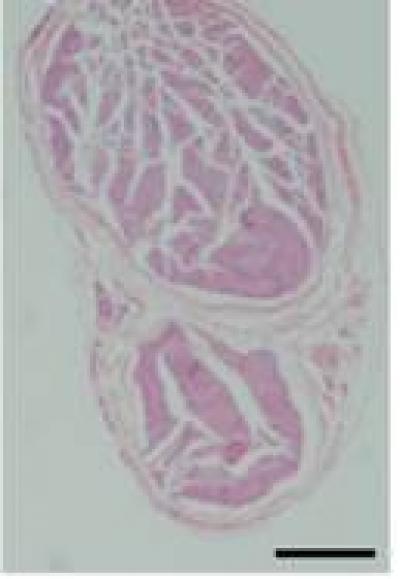

Recently, local scar adhesion after laminectomy always challenges the worldwide scholars engaged in spine surgery. Mitomycin C, a classical anti-tumor drug, has been attempted to be used to effectively inhibit scar adhesion after laminectomy and some encouraging outcomes have been achieved. However, there is evidence that mitomycin C has inherent toxicity and other side effects when it is locally used. Whether mitomycin C can influence peripheral nerve structure and function remains unclear. Dr. Tao Sui and his team, the First Affiliated Hospital of Nanjing Medical University, China reported that mitomycin C, at 0.7 mg/mL, did not produce obvious effect on peripheral nerve function, and mitomycin C at 0.1-0.5 mg/mL did not damage the structure of peripheral nerve. However, mitomycin C at 0.7 mg/mL significantly reduced the thickness of the sciatic nerve myelin sheath. These experimental findings indicate that local application of mitomycin C at low concentrations is safe to prevent scar adhesion following laminectomy, but that at high concentrations (> 0.7 mg/mL) has potential safety risks to peripheral nerve structures. These results were published in Neural Regeneration Research (Vol. 9, No. 8, 2014).

Article: " Potential risk of mitomycin C at high concentrations on peripheral nerve structure," by Tao Sui1, Jinhong Zhang2, Shihao Du1, Changhui Su3, Jun Que4, Xiaojian Cao1 (1 Department of Orthopedics, the First Affliated Hospital of Nanjing Medical University, Nanjing, Jiangsu Province, China; 2 Department of Orthopedics, the Second Hospital of Nanjing, Affliated to Southeast University, Nanjing, Jiangsu Province, China; 3 Department of Orthopedics, Affliated Hospital of Taishan Medical College, Taishan, Shandong Province, China; 4 Department of Intensive Care Unit, the First Affliated Hospital of Nanjing Medical University, Nanjing, Jiangsu Province, China)

Sui T, Zhang JH, Du SH, Su CH, Que J, Cao XJ. Potential risk of mitomycin C at high concentrations on peripheral nerve structure. Neural Regen Res . 2014;9(8):821-827.